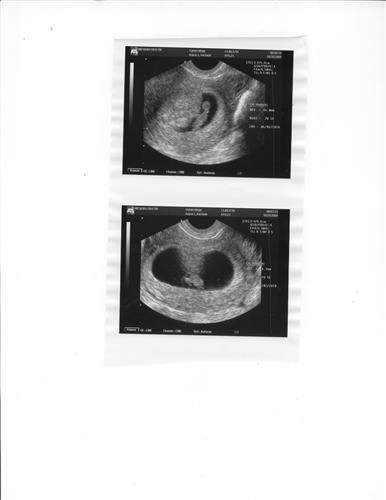

Pregnancy

piggy007

10/21/09